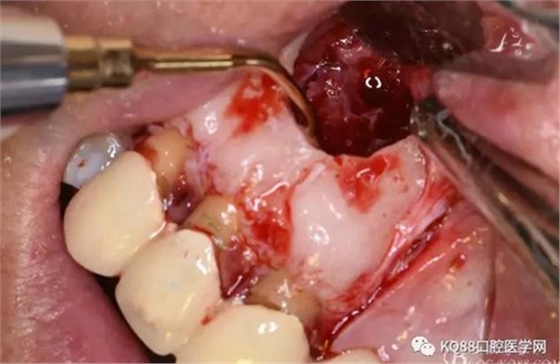

圖11.摘除囊壁后形成的骨腔

圖12.超生骨刀切除12根尖

圖13.根尖倒預(yù)備